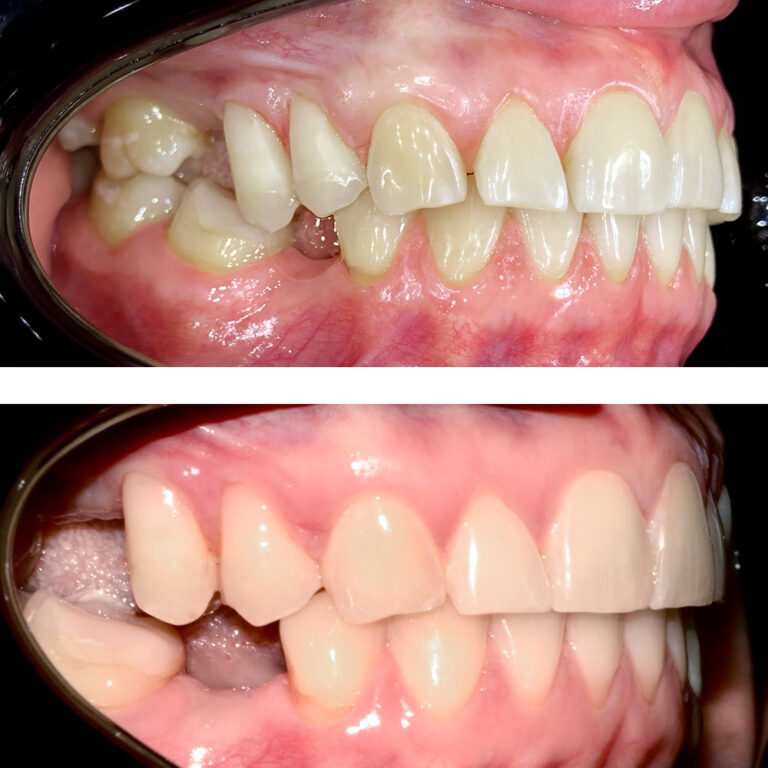

Кейс 23

Иванова Екатерина Сергеевна

Количество кап ВЧ 24

Количество кап НЧ 24

ДО

ПОСЛЕ